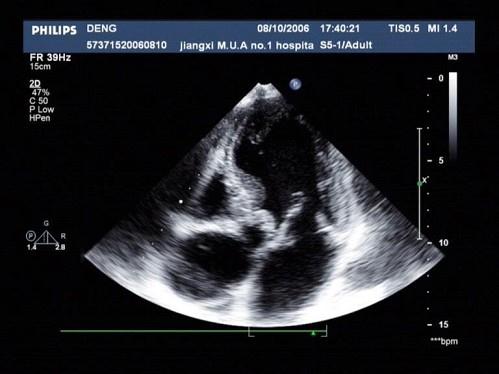

问题 患者,男,50岁,发热半月余,全身不适,乏力,食欲不振。根据超声心动图,最可能的诊断是?(?)

选项 A.风湿性心脏病 B.感染性心内膜炎 C.老年退行改变 D.主动脉瓣狭窄 E.冠心

答案 B